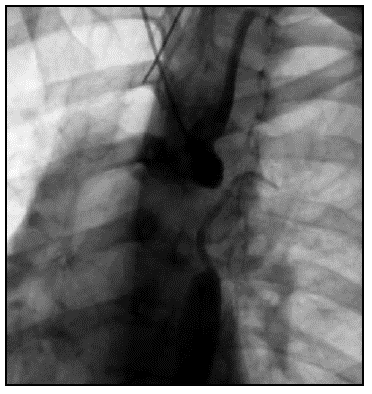

Caso 4.Trazo de onda de pulso arterial anormal, P1 es menor que P2 y el AP es positivo, lo cual indica que hay rigidez marcada, P2 es mayor y está elevando la presión sistólica, de igual manera se evidencia que la presión central es mayor que periférica, otro marcador de rigidez, lo cual se correlaciona con la VOP elevada. Se puede entender el componente mecánico de la endoprótesis en el sistema arterial con poca distensibilidad (compliance) (Figura 2).

El cuarto caso, es una paciente de 68 años con historia clínica de disección de aorta de10 años de evolución y dos correcciones con endoprótesis (Figura 2).

De igual forma, hay cambios en la VOP en pacientes con patología mecánica de la aorta, como son los casos de disección de aorta corregida con endoprótesis o coartación de aorta, a pesar de ser, patologías y pacientes diferentes, sus componentes mecánicos se comportan de igual manera (menos distensibilidad arterial). En el caso de la corrección con endoprótesis, se observan los parámetros severamente elevados, la VOP y los índices evidencian una rigidez severa, la presión arterial central es mayor que la presión arterial periférica. Estos efectos pueden ser causados por las condiciones clínicas de la paciente y la endoprótesis persé. La endoprótesis es de un material menos elástico que la pared vascular y en este caso cubre la aorta ascendente y torácica (región con mayor distensibilidad), lo cual puede correlacionarse con la severidad de la rigidez. Este concepto puede estar presente en los casos de coartación aórtica, en donde la aorta a pesar de ser "joven y elástica", en una porción hay una gran estrechez, lo cual compromete la elasticidad y comportamiento fisiológico normal, por esta razón se puede ver como los parámetros están aumentados, las presiones, VOP y los índices son severamente elevados para la edad. En el caso del paciente después de la corrección con stent, se observa como mejoran los parámetros significativamente.